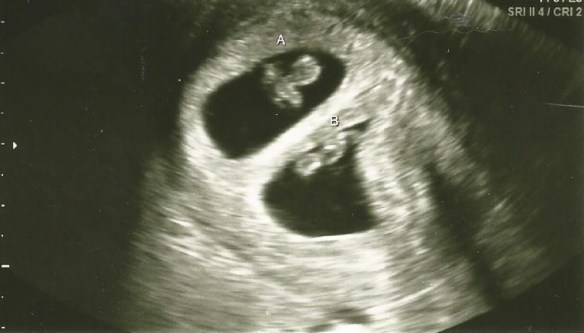

I think that ultrasound was from week 13. We had a LOT of ultrasounds. Which was great, we were very fortunate because I know most people only get to see their little ones a handful of times. But we seriously had one at every appointment, which was a lot, considering we were seeing our OB every 4 weeks and a maternal fetal medicine specialist every 6. Then of course the closer we got to our due date, the more frequent the appointments became. So we had a good amount. I’ll only share my favorites here I promise. Also, the earlier ones are the best, once they get bigger it’s hard to see much.

Above: Baby B on the left, and Baby A on the right at 15 weeks.

Above: Baby A on the left, and baby B on the right. 19 weeks

FINALLY the day came, and first thing was first, they sent us off for an ultrasound with a technician before we saw the doctor.  And this is what we saw:

Week 7 A and B2_cropped

Yes…you are seeing that right…there are two 🙂 A and B. I saw it immediately and started crying and cursing and laughing all simultaneously. Joey thought something was wrong because he was watching my face instead of the screen (and cause he’s a dude and up until this point hadn’t paid attention to other people’s sonograms before and didn’t really know what he was looking at). Then the tech said TWINS!!! And suddenly he understood my reaction.